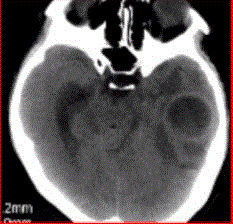

问题 患者女,26岁,头痛、低热10d余,既往有左侧慢性中耳炎病史。CT表现如下图。 脑脓肿的MRS表现,正确的是

选项 A.Cho明显升高 B.NAA未见异常 C.Lac升高 D.乙酸峰、乳酸峰、丁二酸峰升高 E.Lip峰升高

答案 D